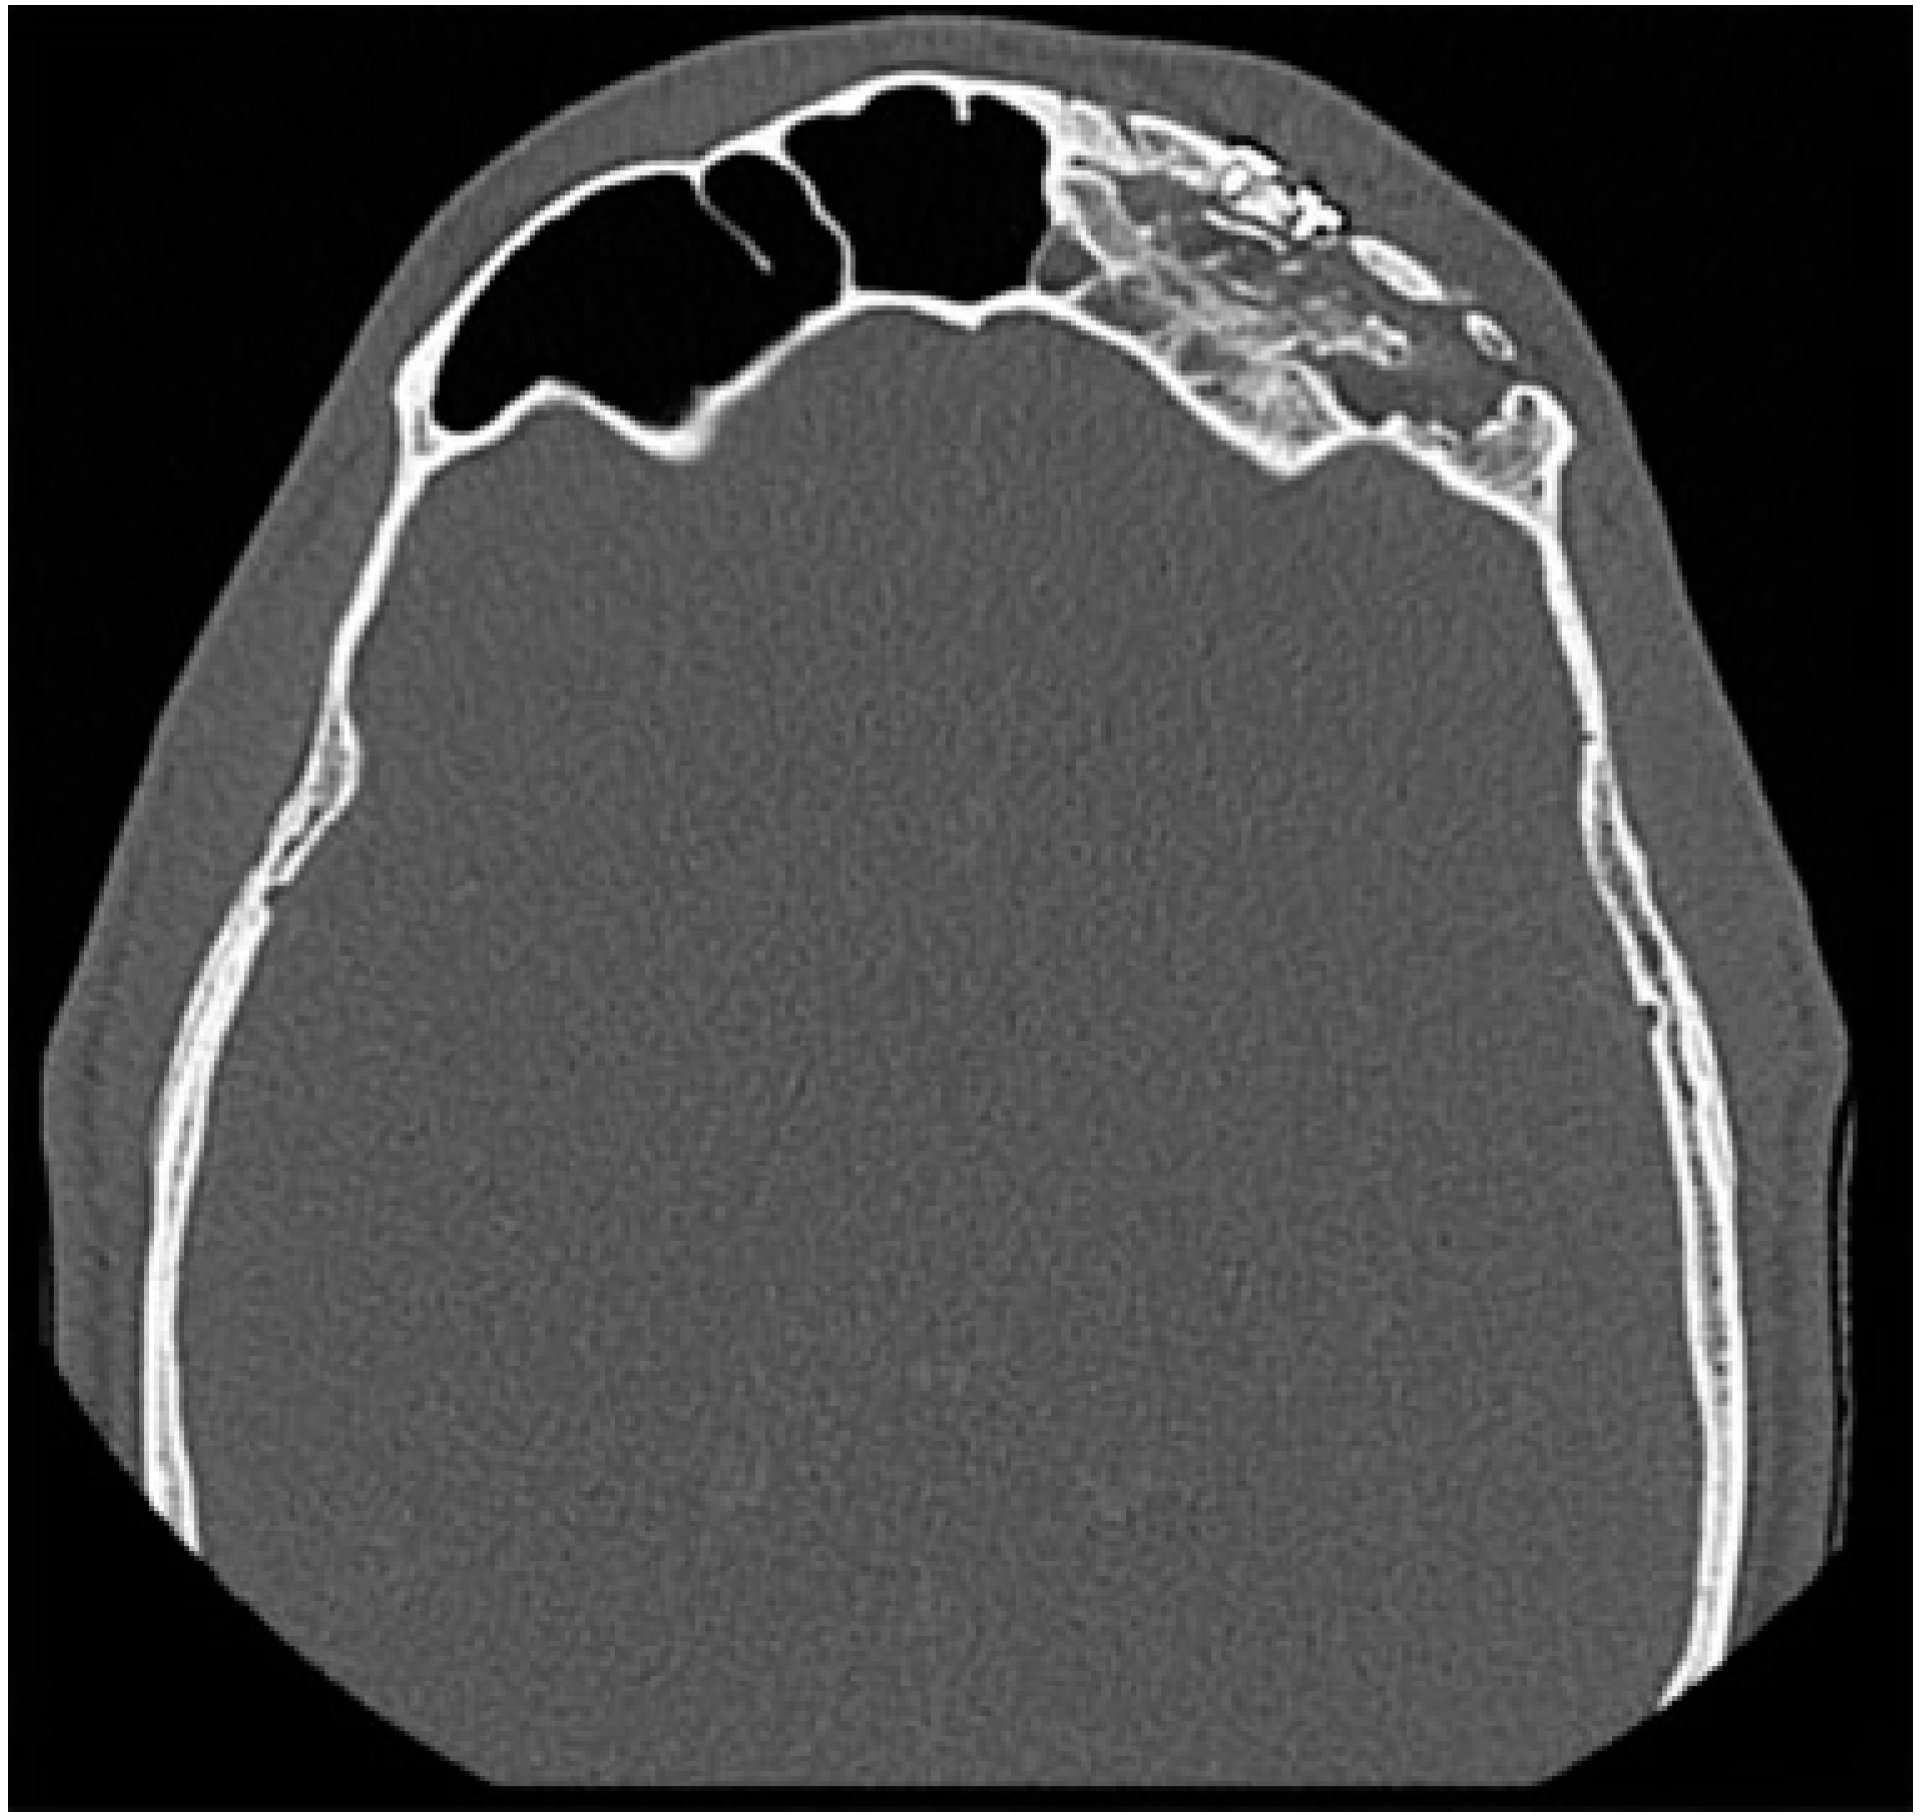

Fractures isolated to the anterior table account for 18–27% of frontal sinus fractures.[3,5,16] The indication for repair has mainly focused on correcting a cosmetic deformity. Without injury to the frontal sinus outflow tract or posterior table, many series have reported on the safety of observation of isolated anterior table fractures.[1,3,4,17,18] The degree of displacement necessitating repair is controversial. The degree of displacement seen on CT imaging may not correlate with the either the visualized or palpated deformity due to overlying edematous soft tissue. It is also difficult to predict the degree of resultant deformity after the acute swelling subsides (Figure 2). Furthermore, physician and patient expectations vary regarding the definition of an “acceptable” forehead contour. With observation, bony remodeling and scarring over an intact periosteum may subsequently hide any cosmetic deformity, especially in pediatric patients [19].

Figure 2.

CT in the axial plane demonstrating a comminuted, displaced bilateral fracture of the anterior table of the frontal sinus fracture. In the acute setting, significant soft tissue edema may obscure a palpable deformity.